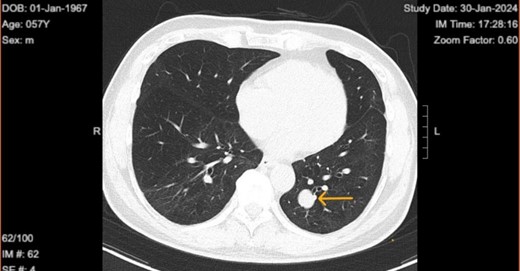

Upon diagnosis of SFT, the patient was referred to a surgeon for consideration for left lower wedge resection via video-assisted thoracoscopic surgery. However, the treatment consisted of monitoring of the tumor with biannual CT scans. Immediate surgical intervention was not performed, as the tumor remained stable in size, asymptomatic, and showed no signs of aggressive behavior. The latest CT on 30 January 2024 shows the tumor size to be 1.9 × 1.6 cm (initial size 1.5 × 1.3 on 21 May 2021) with no accompanying symptoms (Figs 2 and 3).

Chest computed tomography in 2024 shows well circumscribed solitary lung tumor of 1.9 × 1.6 cm in size.